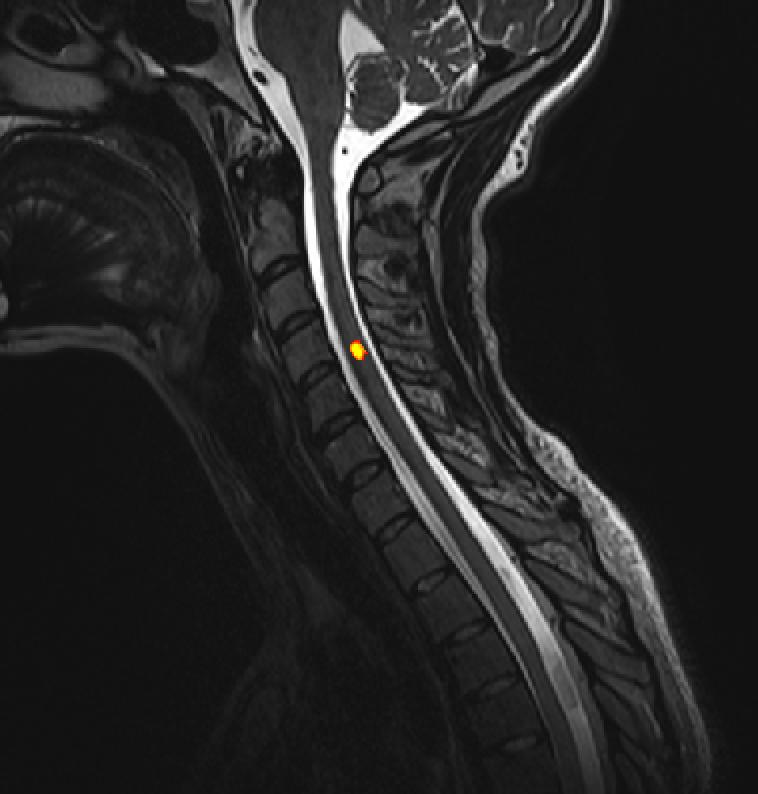

Des scientifiques de l’EPFL ont développé une technique non invasive qui dévoile la dynamique des circuits spinaux avec une précision sans précédent. Une première dans le domaine de l’imagerie fonctionnelle à résonance magnétique, qui pourrait contribuer à diagnostiquer les lésions ou les malfonctions de la moelle épinière.

Les scientifiques de l’EPFL ont conjugué des protocoles spécialement adaptés à l’IRMf de la moelle épinière à des techniques d’analyse de pointe, ce afin de démêler ces signaux et de pouvoir clairement observer la moelle épinière en action. Des tests sur 19 sujets sains ont permis d’obtenir des images sans précédent de son architecture fonctionnelle. Pour la première fois, les scientifiques ont montré à quel point la moelle épinière est dynamique, même chez des sujets au repos. Ils publient aujourd’hui leurs résultats dans la revue Neuron.

Quant aux volontaires, ils n’ont qu’à s’allonger dans un scanner IRMf et rester immobiles pendant la procédure, généralement d’une durée d’environ 10 minutes. Les images du scan sont analysées pour produire une représentation en quatre dimensions — espace et temps — afin d’observer la dynamique des circuits spinaux à l’intérieur de l’anatomie du sujet.

Vu sa place centrale, à l’interface entre le cerveau et le reste du corps, la moelle épinière est un acteur majeur des comportements humains. Dans cette étude, les scientifiques se sont particulièrement intéressés à son niveau cervical, une région cruciale pour le contrôle musculaire des bras et des mains. Leur approche pourrait permettre de comprendre comment ces circuits spinaux s’organisent pour offrir la large panoplie de mouvements que nous accomplissons au quotidien.